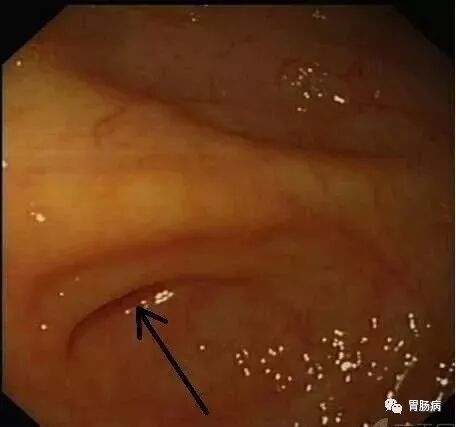

ERAT术后 内镜下观察阑尾的恢复情况良好,水肿消失。

图A示阑尾开口水肿消失(箭头);